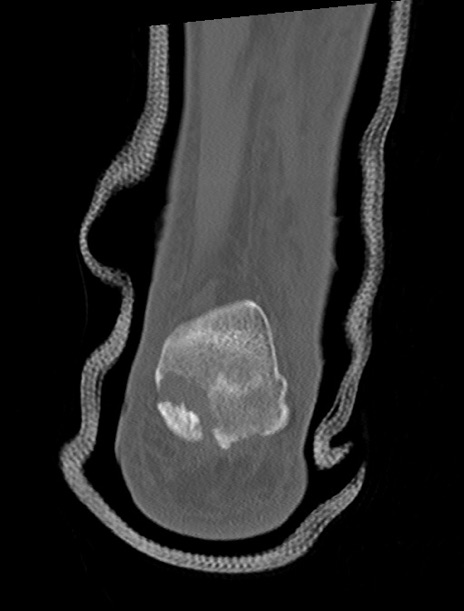

症例37 左足関節CT(冠状断像)

左足関節CT

3D再構成